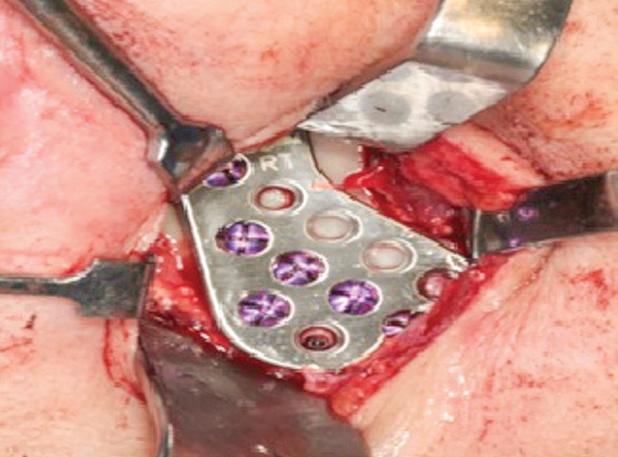

A paciente foi submetida à reconstrução total bilateral com próteses de estoque do sistema Biomet (Biomet 3i do Brasil Ltda., São Paulo/SP, Brasil). Foram realizados, bilateralmente, acessos pré-auricular e retromandibular, condilectomia e, por fim, instalação das próteses de estoque. A sequência da instalação das próteses consistiu em primeiro o componente fossa e, depois, o componente mandibular (Fig. 2). O paciente encontra-se aos cinco anos de pós-operatório, com uma boa abertura de boca e oclusão preservada e sem dor (Fig. 3).

Figura 2: A) Acesso pré-auricular direito. B) Acesso pré-auricular esquerdo. C) Componente mandibular direito instalado na face lateral do ramo da mandíbula através do acesso retromandibular. D) Componente fossa direito instalado na base do crânio através do acesso pré-auricular. E) Componente mandibular esquerdo instalado na face lateral do ramo da mandíbula através do acesso retromandibular. F) Componente fossa esquerdo instalado na base do crânio através do acesso pré-auricular.